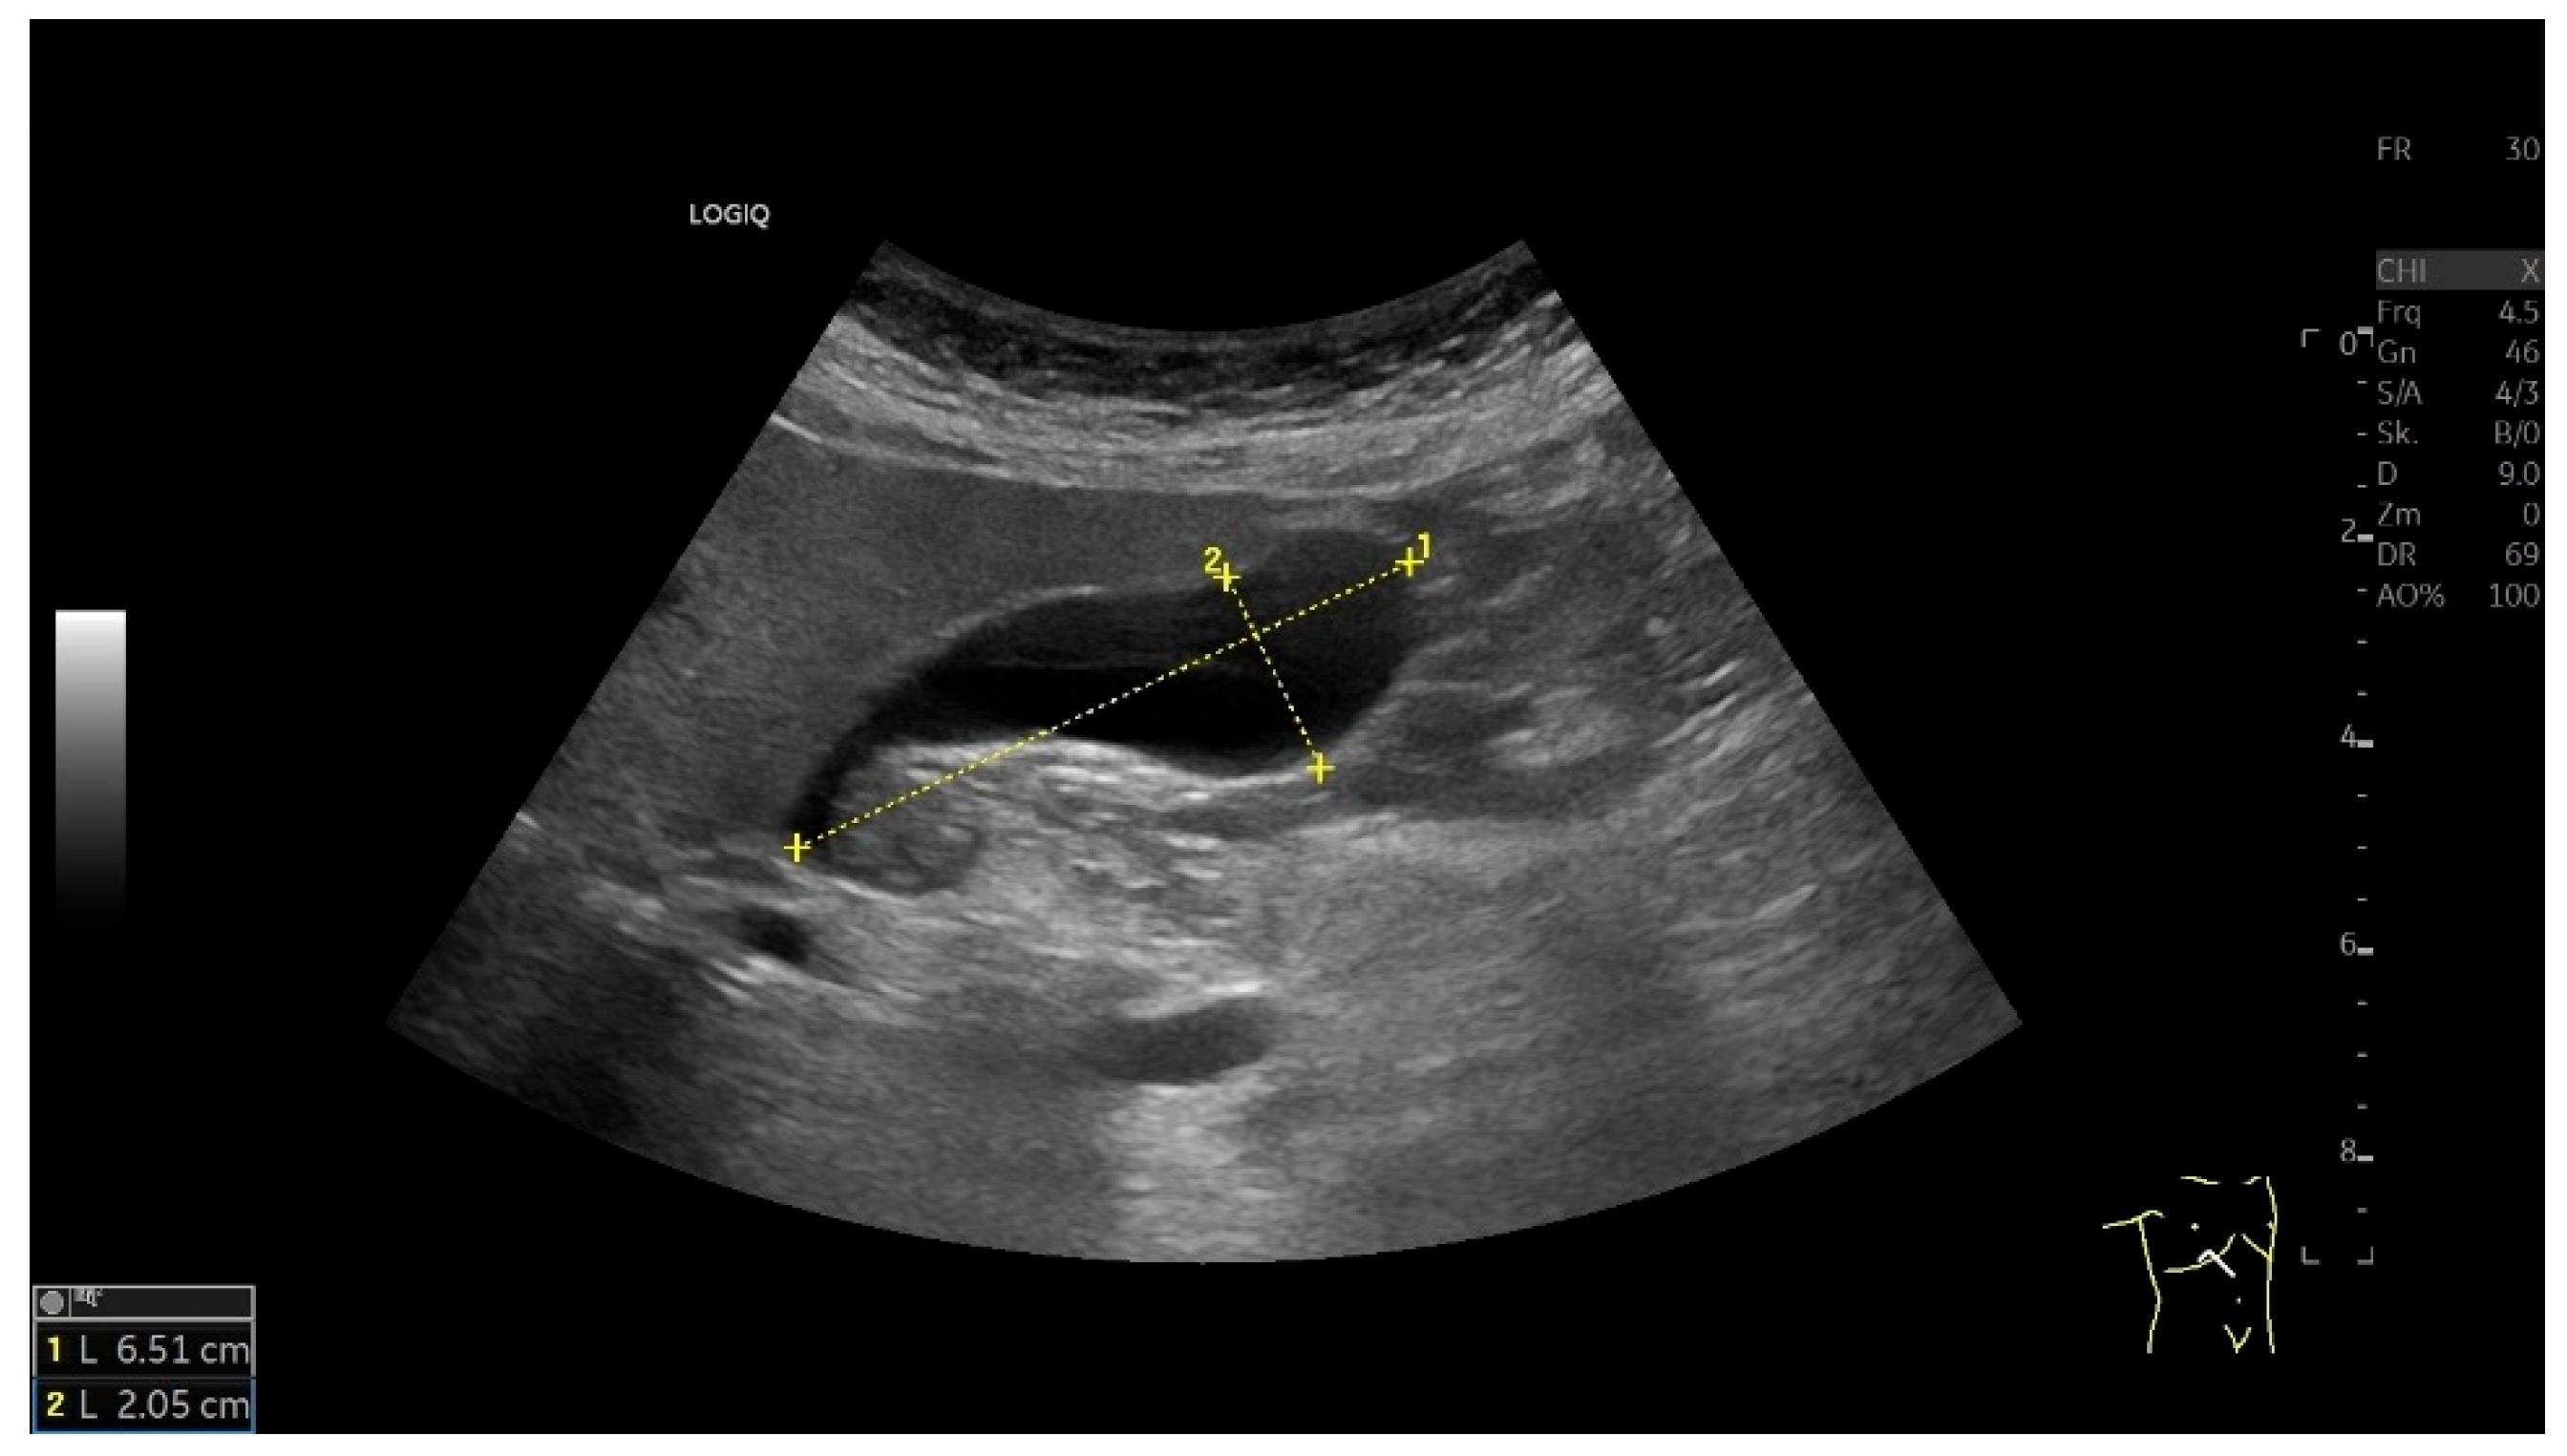

3.1. Gallbladder Size (Length and Width)

| Length × width × depth | <10 × 4 × 4 cm [5,32,33,34]. |